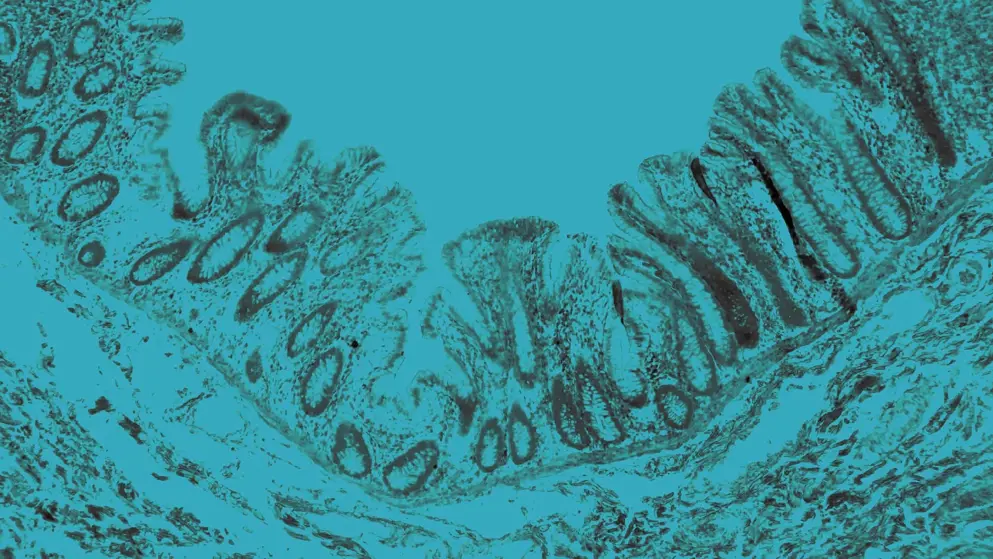

IBD includes Crohn’s disease and ulcerative colitis, both involving chronic, immune-mediated GI inflammation. Crohn’s disease may involve any segment from mouth to anus and is characterized by transmural inflammation and skip lesions. Ulcerative colitis is confined to the colon and rectum, and involves continuous mucosal inflammation.

IBS is a diagnosis of exclusion, reliant on symptom-based criteria and the absence of biochemical abnormalities. By contrast, IBD diagnosis necessitates a multistep strategy incorporating serologic and fecal biomarkers, cross-sectional imaging, endoscopic evaluation, and histology to confirm inflammation and structural changes in the GI tract.

Despite overlapping symptoms, IBS lacks objective inflammatory markers, while IBD typically presents with detectable mucosal inflammation.